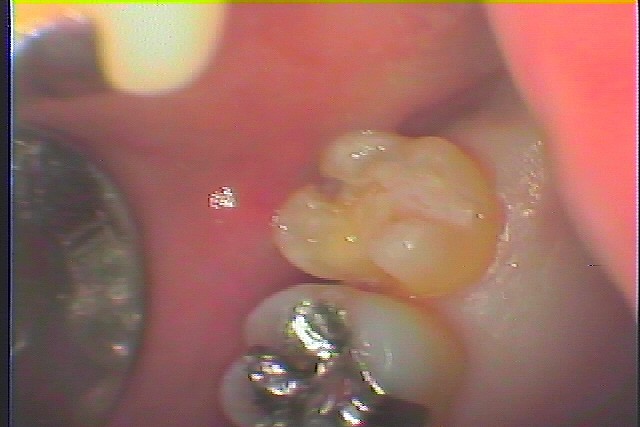

左上7番の虫歯治療の実際 白いセラミック治療へ|お知らせ |広島市安佐南区の歯科医院 左上7番の虫歯治療の実際 白いセラミック治療へ トップ お知らせ・ブログ お知らせ 左上7番の虫歯治療の実際 白いセラミック治療へ 左上7番の虫歯治療の実際 白いセラミック治療へ この銀歯の下が虫歯になっています 中にはこのように虫歯が、、、 大きく黒く虫歯になっています 虫歯を除去していきました 虫歯を取ると中の組織は黄色の象牙質が出てきます CR樹脂にて覆罩を行い型取りを行っていきます このようにきれいに仕上がりました Web診療予約 初めての方へ 選ばれ続ける理由 院内設備について 歯が痛いしみる一般歯科 歯がぐらぐらする歯周病 健康な歯を保ちたい予防歯科 子供の虫歯予防をしたい小児歯科 銀歯をセラミックに審美歯科 白い歯を目指しませんか?ホワイトニング 矯正専門医がいるので安心矯正歯科 抜けた歯を補いたいインプラント・入れ歯 医院案内 スタッフ紹介 メリィハウス歯科クリニックオフィシャルホームページ ラベンダー歯科クリニックオフィシャルホームページ お知らせ・ブログ ホーム 診療科目 一般歯科 歯周病治療 予防治療 小児歯科 審美治療 ホワイトニング 矯正歯科 入れ歯・インプラント マウスピース矯正 初めての方へ 院長・スタッフ 設備紹介 医院案内・アクセス メニューを閉じる